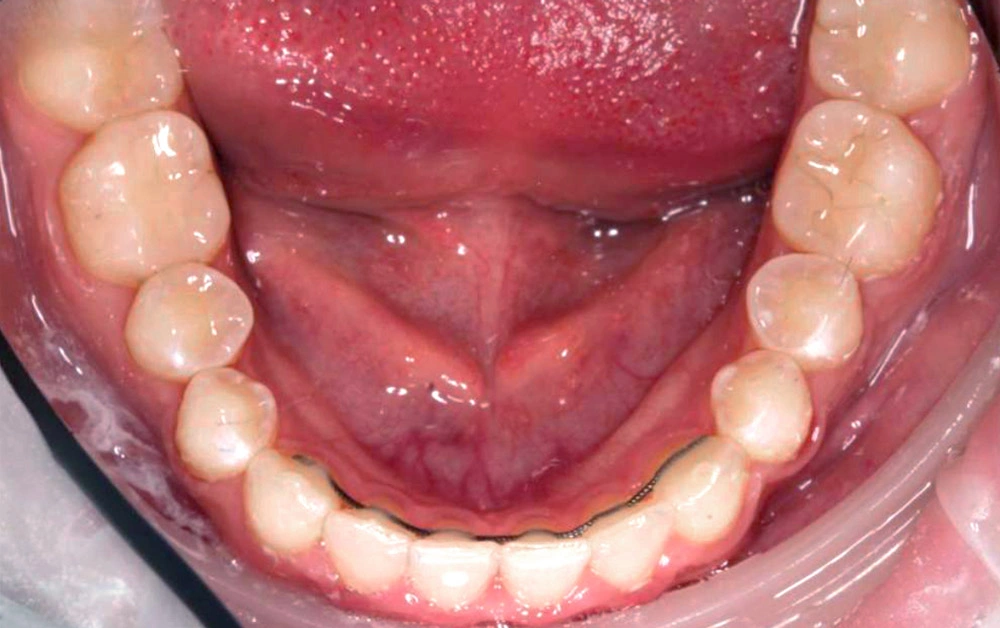

Глубокий прикус - Кейс 5

Эффективность устранения дефекта прикуса посредством элайнеров FlexiLigner.

16

Количество кап НЧ

Количество кап ВЧ

Результаты лечения